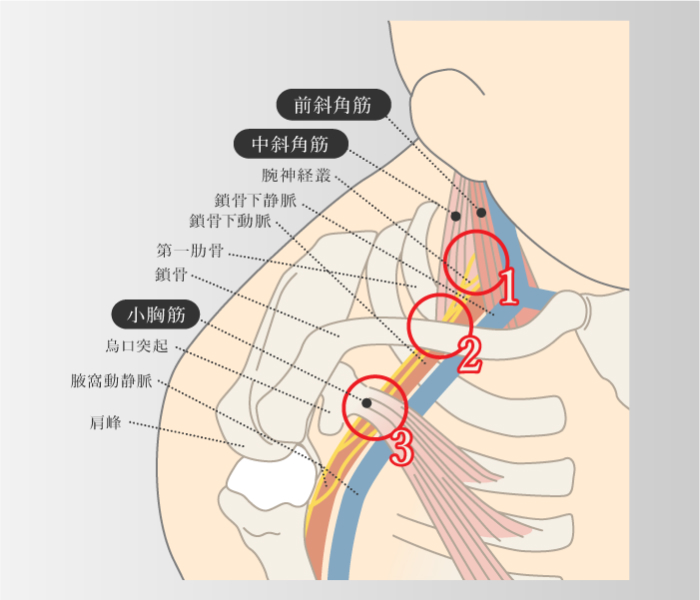

胸郭出口症候群

-

①前斜角筋と中斜角筋の間、②鎖骨と第1肋骨の間の肋鎖間隙、③小胸筋の肩甲骨烏口突起停止部の後ろを走行する鎖骨下動脈が絞扼される。

その絞扼部位によって、斜角筋症候群、肋鎖症候群、小胸筋症候群(過外転症候群)と呼ばれ、総称して胸郭出口症候群と言う。神経障害と血流障害に基づく上肢痛、上肢のしびれ、頚肩腕痛を生じる疾患の一つ。